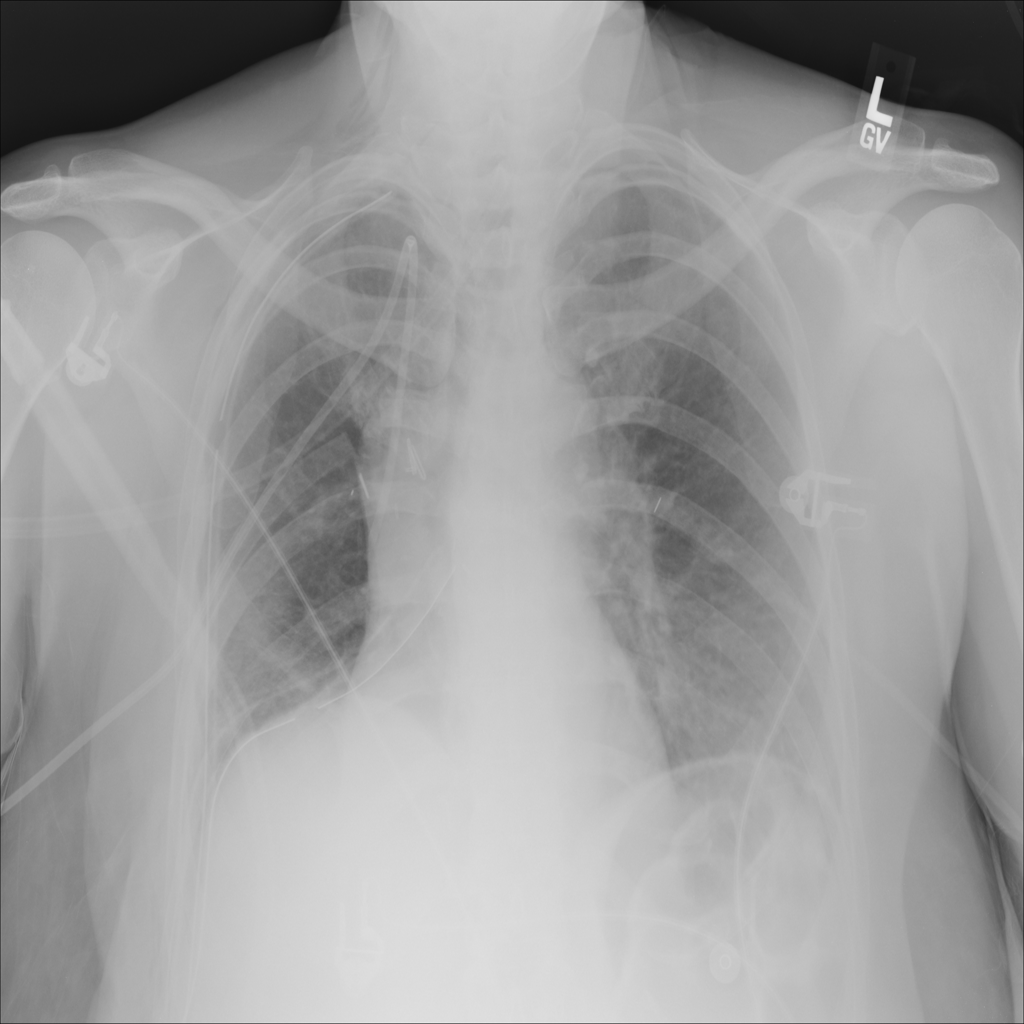

PAT-0E82 · IMG-000Emphysema

PAT-0E82 · IMG-000

AP